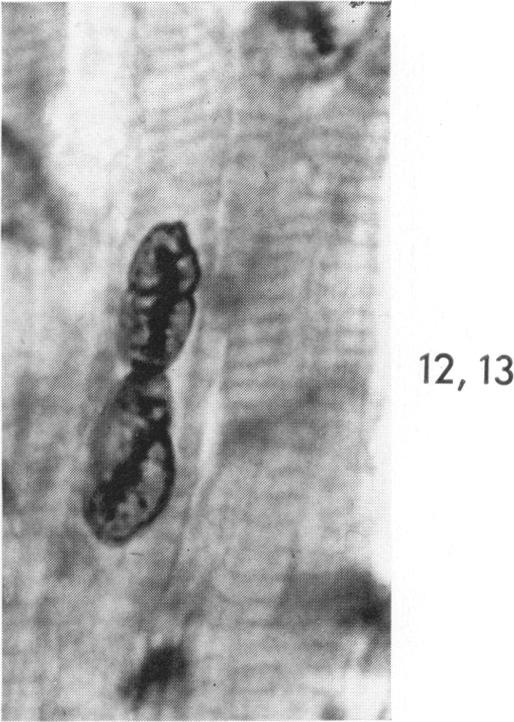

Occurrence of caterpillar nuclei within normal immature and normal appearing and altered mature heart muscle cells and the evolution of Anitschkow cells from the latter.

Am J Pathol. 1966 Jun;48(6):931-57.